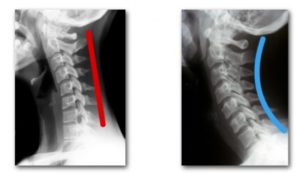

ストレートネックとは頸椎の前彎(生理的な彎曲)が失われて、まっすぐになってしまっている状態のことをいいます。

本来であれば、彎曲によって頭の重さを分散させ、衝撃を和らげる役割をしています。